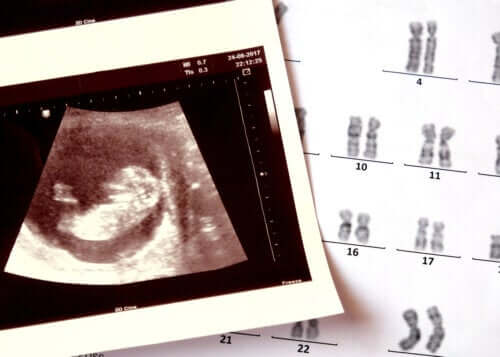

L’anencéphalie est une maladie congénitale qui consiste en l’absence de développement de certaines parties du système nerveux et du crâne du bébé.

Cet état de santé se classe dans les anomalies du tube neural. Un groupe de pathologies congénitales, dont le spina bifida.

Des altérations chromosomiques (structures qui abritent tous les gènes dans les cellules) et certaines mutations ponctuelles pourraient contribuer à son apparition. Il a également été étudié que l’exposition à certaines toxines environnementales pourrait être déterminante. Bien qu’à l’heure actuelle les résultats des investigations ne soient pas concluants.